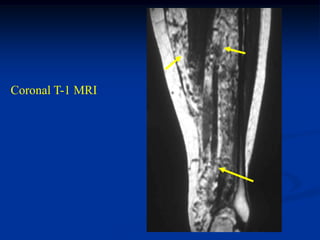

Case #270.3 Intraneural lipoma sciatic nerve 65 year old female with 3 yr history of large painless mass in posterior thigh

Case #1190.2 33 yearold female with painless lump at ankle for 1 year

Sag T-1 PD Gad